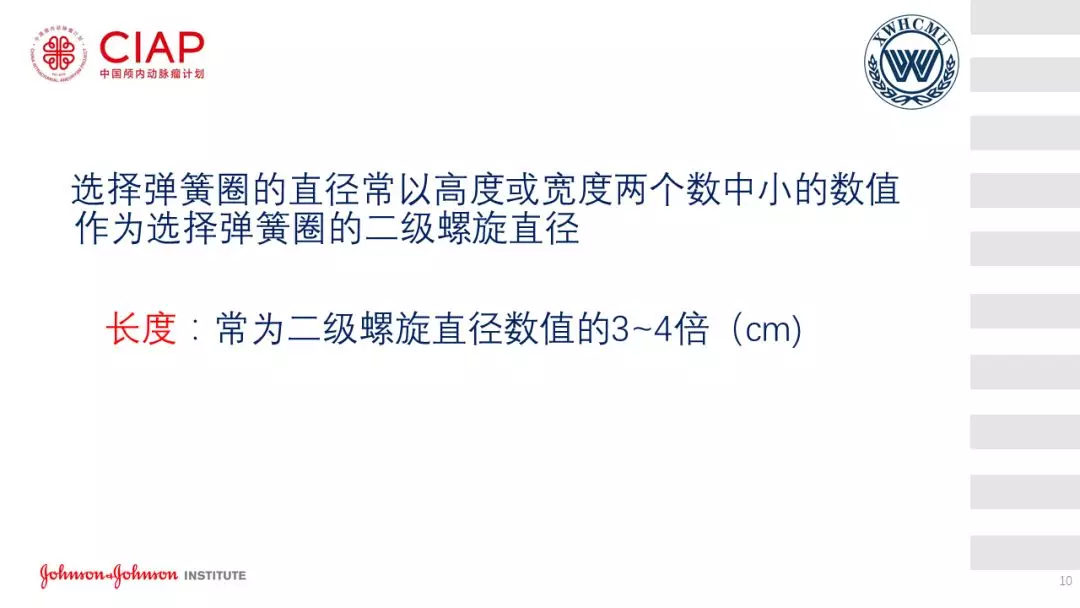

张鹏教授:不同辅助方法下栓塞动脉瘤弹簧圈的选择